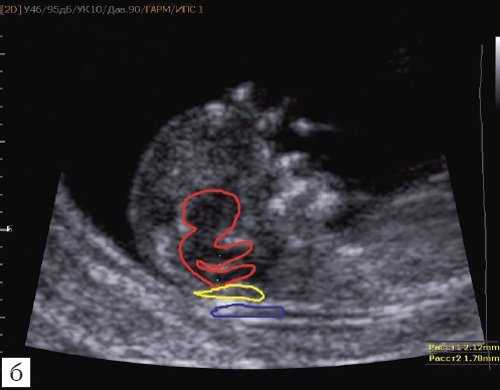

Особенности визуализации изложенных выше структур в данном сроке позволили нам выделить и назвать новый ультразвуковой маркер нормальной ультразвуковой анатомии мозга плода. Структуры головного мозга плода в этой области схожи с осьминогом, у которого есть голова и две приблизительно равновеликие по диаметру ножки, представляющие собой ствол мозга и IV желудочек. Ниже ножек "осьминожки" визуализируется 2 "подушки осьминожки" - это два анэхогенных пространства - большая цистерна и воротниковое пространство (рис. 2, б).

Так как речь идет о сроках первого скрининга, т.е. раннего осмотра, новый ультразвуковой маркер мы назвали "осьминожкой" (рис. 3).

а) Стрелками указана голова "осьминожки" - диэнцефалон (таламус).

б) Красный цвет - диэнцефалон (таламус), со стволом мозга (верхняя ножка) и IV желудочком (нижняя ножка); желтый цвет - большая цистерна головного мозга; синий цвет - воротниковое пространство.

Как сказано выше, имеет значение и измерение ножек "осьминожки", так среднее значение диаметра нижней ножки, т.е. IV желудочка в зависимости от КТР в срок 11-14 недель варьирует от 1,5 до 2,5 мм (рис. 4).

Рис. 4. Измерение и взаимоотношение ножек "осьминожки" - ствола мозга и IV желудочка у плода, беременность 12 недель.

Измерение ножек "осьминожки".

Красный цвет - диэнцефалон (таламус), со стволом мозга (верхняя ножка) и IV желудочком (нижняя ножка); желтый цвет - большая цистерна головного мозга; синий цвет - воротниковое пространство.